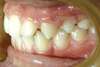

Vues avant le traitement à l'âge de 6 ans

Vues après le traitement